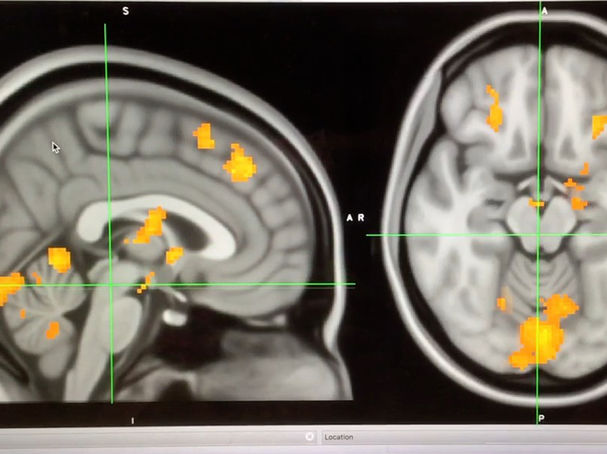

A series of recent studies have found that listening to music engages broad neural networks in the brain, including brain regions responsible for motor actions, emotions, and creativity.

Two previous studies identified the broad range of neural networks that are engaged when we listen to music. A 2009 study from the University of California, Davis mapped the brain while people listened to music and found specific brain regions linked to autobiographical memories and emotions are activated by familiar music. The UC Davis study titled, "The Neural Architecture of Music-Evoked Autobiographical Memories," was published in the journal Cerebral Cortex.

When Janata studied the fMRI images and compared them to these self-reported reactions, he discovered that the degree of salience of the memory corresponded to the amount of activity in the upper (dorsal) part of the medial prefrontal cortex. This correlation supports Janata's hypothesis that this brain region helps link music and memory.

Janata was also able to create a model for mapping the tones of a piece of music as it moves from chord to chord and into and out of major and minor keys. By making tonal maps of each musical excerpt and comparing them to their corresponding brain scans, he discovered that the brain was tracking these tonal progressions in the same region as it was experiencing the memories: in the dorsal part of the medial prefrontal cortex, as well as in regions immediately adjacent to it. And in this case, too, the stronger the autobiographical memory, the greater the "tracking" activity.

The researchers discovered that listening to music activates wide networks in the brain, including areas responsible for motor actions, emotions, and creativity. Their method of mapping revealed complex dynamics of brain networks and the way music affects us. For this study, participants were scanned with functional Magnetic Resonance Imaging (fMRI) while listening to a stimulus with a rich musical structure, a modern Argentinian tango.

The Finnish researchers correlated temporal evolutions of timbral, tonal, and rhythmic features of musical stimulus. While timbral feature processing was associated with activations in cognitive areas of the cerebellum, and sensory and the default mode network gray matter of the cerebral hemispheres, musical pulse and tonality processing recruited cortical and subcortical cognitive, motor and emotion-related circuits.

The researchers found that music listening recruits the auditory areas of the brain, but also employs large-scale neural networks. For instance, they discovered that the processing of musical pulse recruits motor areas in the cerebellum and cerebrum, supporting the idea that music and movement are closely intertwined.

Limbic areas of the brain, known to be associated with emotions, were also found to be involved in rhythm and tonality processing. Processing of timbre was associated with activations in the so-called default mode network, which is assumed to be associated with mind-wandering and creativity.